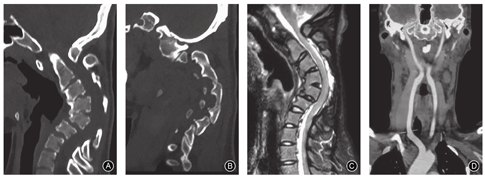

CT示齿突超过Chamberlain线5 mm,寰齿前间距为7.7 mm,牵引下寰齿前间隙减少至6 mm。寰齿侧间距:左侧5.4 mm,右侧6.7 mm。枕颈融合畸形(寰椎后弓与枕骨融合);C3~C5椎体前缘骨桥形成,且C2,3、C3,4和C4,5椎间隙骨性融合;C2~C6后方椎板及关节突关节融合(图2A,B)。

MRI示脊髓前方受压,脑脊液透亮带消失(图2C)。

肺通气功能检查示肺通气功能及换气功能均正常。颈部血管CTA检查示双侧椎动脉走形及与周围组织毗邻关系基本正常(图2D)。颈椎CT及三维重建评估患者椎弓根发育情况,未见明显的椎弓根异常情况(图3)。CT示椎体无明显的楔形变,椎间隙中部高度C3,4为4.8 mm、C4,5为4.7 mm、C5,6为6.2 mm,C5椎体后方移位,C6,7椎间隙呈前宽后窄。